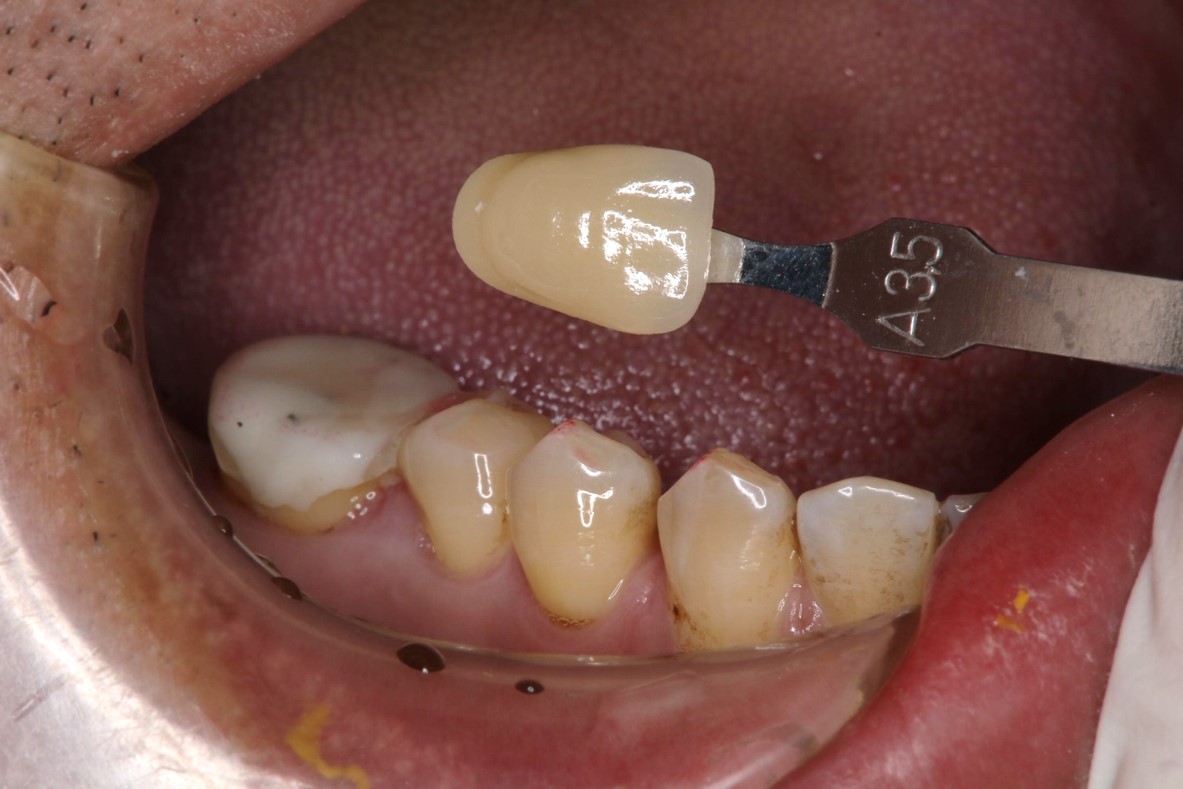

冠塊體牙齒製備

照相比色